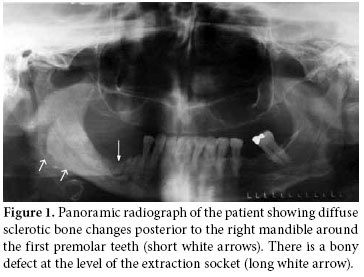

In September 2008, a 58-year-old female diagnosed with AS in 1973 was referred to Ege University Hospital, Department of Physical Medicine and Rehabilitation complaining of pain and discomfort in the right mandible. These symptoms had started in May 2008 following a tooth extraction. The extraction socket did not heal, even after eight weeks, despite antibiotherapy. Besides the pain and discomfort, she experienced the presence of some particles in the tooth extraction socket of her right mandible which were probably autogenous bone. A panoramic radiograph was taken 10 weeks later in July 2008 which revealed irregularity and diffuse sclerotic bone changes in the trabecular bone structure of the right mandible as well as a bony defect at the level of the extraction socket (Figure 1). A sample obtained from the exposed area was sent for culture to the microbiology laboratory due to the suspicion of dental infection/abscess. Oral flora microorganisms grew in the culture.